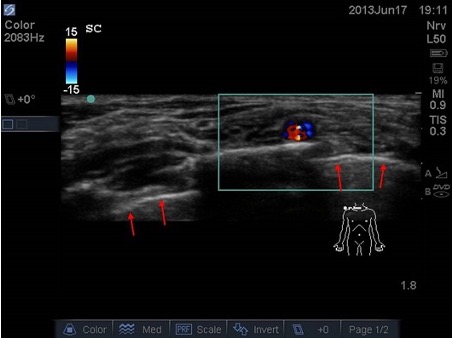

- Identify nearby structures (blood vessels, bowel, bone, pleura) which allows you to avoid complications (especially in small children where target structures and nearby structures are in immediate proximity or very superficial) – example 2, supraclavicular plexus in neonate: very little space between plexus, vessels, pleura, ribs.